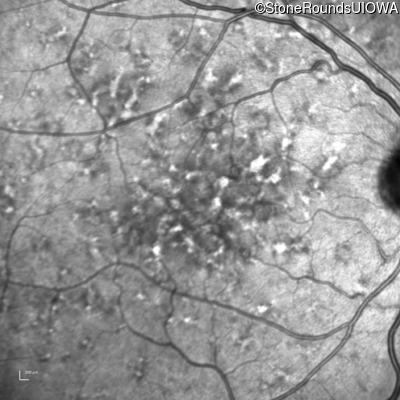

Age at visit: 49 years

OD OS

This 49 year old man was first told he had a fundus abnormality on a routine eye exam at age 34. Ten years later he noticed some distortion just superior to fixation.